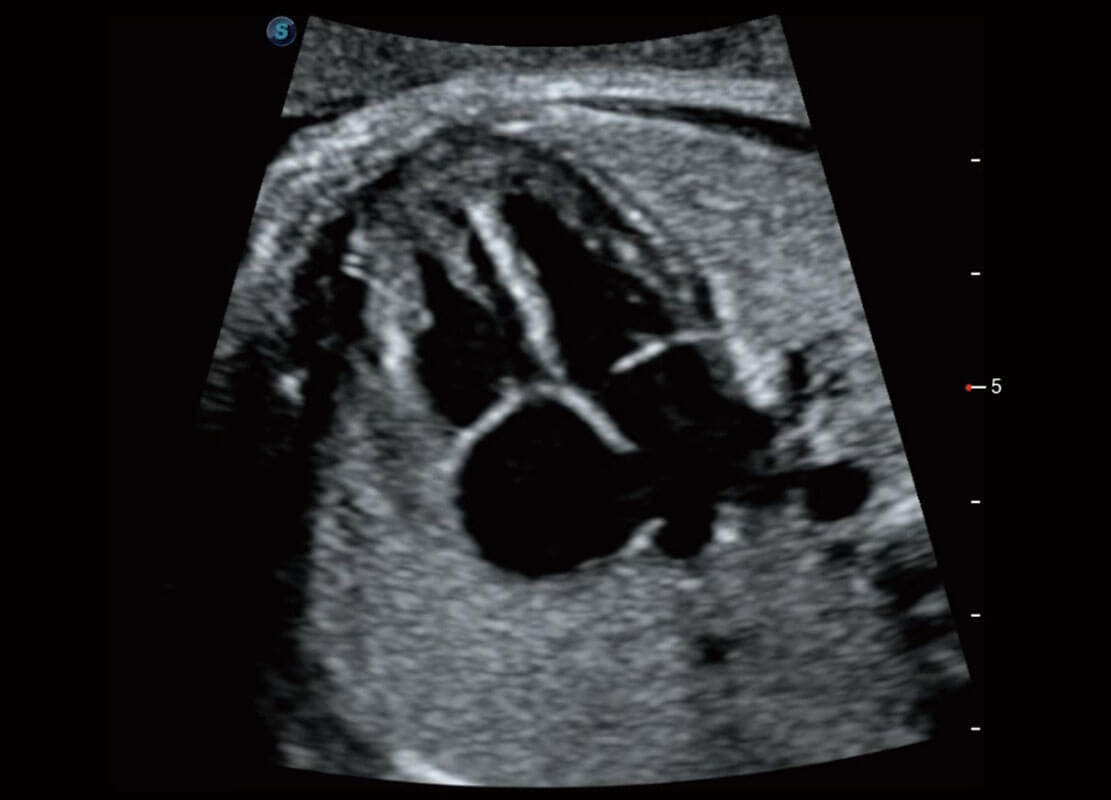

腔内妇科-宫腔分离

腔内妇科-卵巢

腔内三维-宫内节育器

腔内三维-光影成像

P60优异的图像质量搭载专科探头,在妇科基础疾病的诊断、卵泡生长的监测、输卵管通畅情况的判别等方面为您提供生殖应用方案。